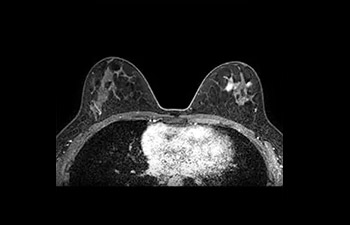

Imágenes de mama

con Compressed SENSE